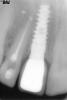

котик Опубликовано 12 мая, 2009 Автор Поделиться Опубликовано 12 мая, 2009 коронка к перфорации никакого отношения не имеет.Ничем ее не улучшит ,но не ухудшит.Проблемы могли быть как в одном,так и в другом случае.Наверное это нужно было врачу обсудить с Вами до начала лечения,а так же договориться,за чей счет банкет будет в каждом случае.А дальше Вы в руках Божьих и того.кто с Вами работает. Выкладываю имплант который мне поставили год назад несто зуба с неправильным штифтом, , когда начинаю кусать этим зубом, испытываю некоторое давление и дикомфорт,. Хотя в нормальном состоянии когда не кусаю им, все нормально вроде. Это почему так? От того что он такой высокий? Или еще не привыкла? На мой взгляд какой то он огромный... Ссылка на комментарий

Bier Опубликовано 12 мая, 2009 Поделиться Опубликовано 12 мая, 2009 Котик, вот честно ваш взгляд на размер имплантата ну мало кого волнует он немного глубоковато поставлен отсюда и проблемы с десной скорее всего. Ссылка на комментарий

Dr. Surkin Опубликовано 12 мая, 2009 Поделиться Опубликовано 12 мая, 2009 Котик, вот честно ваш взгляд на размер имплантата ну мало кого волнует он немного глубоковато поставлен отсюда и проблемы с десной скорее всего. Проблема с десной из-за резорбции наружной кортикалки естесс-но.Насчет глубины... - посмотрите у Фури - примерно также глубоко имплантат стоит:http://s52.radikal.ru/i136/0905/9c/33766e1c27b5.jpg Если бы иплантат не стоял бы так "глубоко" в данном случае мы просто бы увидели абатмент или шейку имплантата. Уж не знаю как насчет удаления имплантата - сомневаюсь в этой необходимости. Наверное надо пробовать либо снимать коронку, добавлять мягких тканей и протезировать заново, либо поставить заглушку и попробовать как-то поверх добавить кости. - ну что-нибудь в этом роде.Сам так не делал - поэтому только теоретизирую. Ссылка на комментарий

Dr. Surkin Опубликовано 12 мая, 2009 Поделиться Опубликовано 12 мая, 2009 (изменено) Саш, мягких тканей без кости не будет.Увеличить объем ака Ван Дорен? Не уверен,что результат не будет иметь рецидива."Это нога....кого надо нога...." - цитата к/ф "Берегись автомобиля" Сереж, я прекрасно знаю про кость. В то же время рецессии закрывают соединительнотканным трансплантатом, когда кости тоже нет. Насчет ноги - нам пока неизвестно направление имплантата. Отсюда вытекает следствие - если он стоит криво - сильно вестибулярно, то возможно для эстетики придется его удалять и проходить весь сложный путь с подсадками и т.д.Однако я очень сомневаюсь в достаточно эстетичном результате после всех этих "процедур".Эстетические случаи ты показывал первичные, а не после удаления имплантатов и прочей маяты. Это две большие разницы. Если стоит ровно - что скорее всего так - судя по рассказу пациентки его ставили непосредствнно в лунку, то смысл удалять его? Проще снять абатмент и закрыть заглушкой, после чего провести аугментацию. Изменено 12 мая, 2009 пользователем Dr. Surkin Ссылка на комментарий